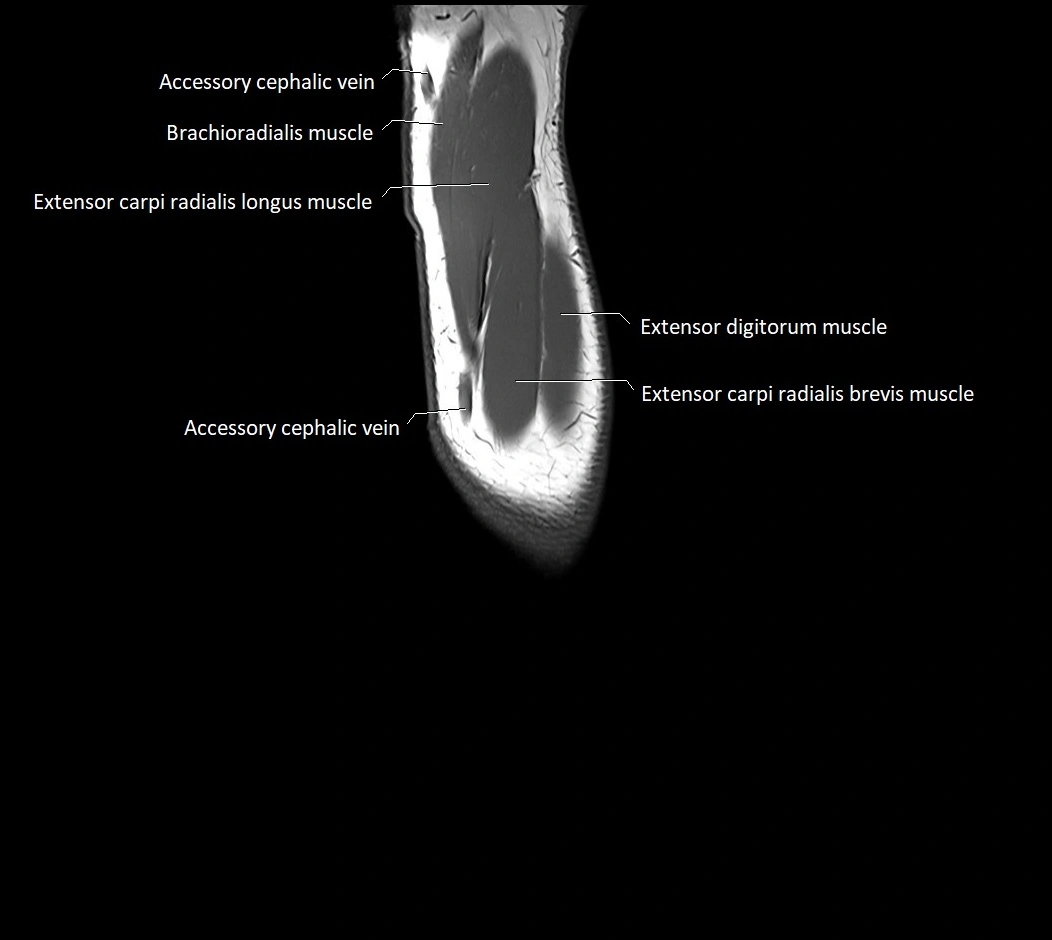

MRI images

image